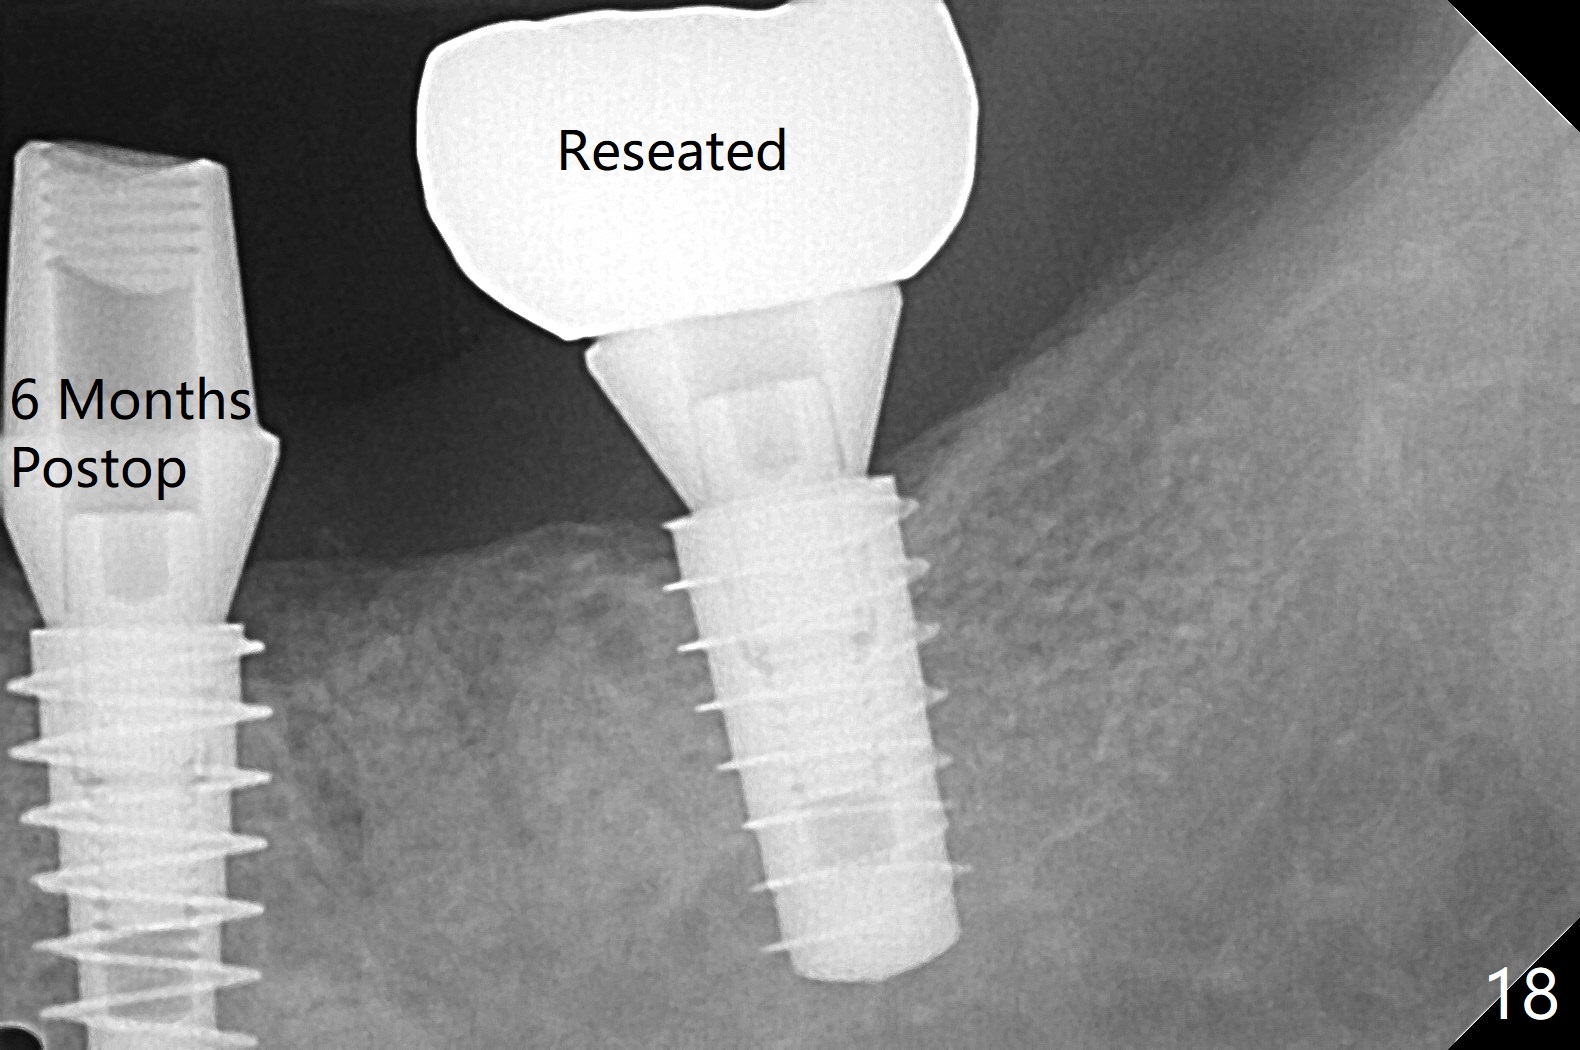

Venopuncture is conducted (Fig.1) for PRF and sticky bone (cortical chip and .5 cc ß-TCP). After use of proximators at #19, cowhorn forceps are applied, resulting in metal crown dislodgement. Since there is distal bone loss, distal socket sheath is contemplated. The tooth is sectioned. When an elevator is inserted between the roots, the distal root is loosened first. The 2 roots are removed, revealing a rounded end septum (Fig.2 S) and a larger distal socket. To avoid osteotomy deviation over the septum, a 12 mm bone trimmer is used, followed by point drill (Fig.3 *). But the lower half of the implant is deviated mesial (Fig.4) with decreased torque (~ 10 Ncm). To overcome this misfortune, the roots should not be removed until osteotomy is finished. Dual zones of bone graft is conducted. Sticky bone is placed until the plateau of the implant with a healing screw in place (Fig.4 * (bone zone)). After placement of a pair abutment, the same bone graft is packed until the margin of the abutment (Fig.5 * (soft tissue zone)). An immediate provisional is fabricated to close the socket with a piece of PRF as well. Fig.6-11 explains why the lower half of the implant deviates to the mesial socket, while Fig.12-16 illustrates how to prevent the deviation. After extraction of #19 (Fig.6,7), the crest of the septum is flattened (Fig.8 arrowhead) to prevent the initial deviation (Fig.9 red line). When a drill reaches a space (a socket, mesial in this case), the drill is deflected to the least resistant area (Fig.10 a bent red line), leading to the implant deviation apically (Fig.11 green). To prevent the apical deviation, therefore, the roots of the affected tooth is temporarily not removed (Fig.12). The osteotomy should not deviates with surgical guide because of similar density between the tooth and the bone (Fig.13). When the osteotomy is finished (Fig.14), the roots are extracted (Fig.15). The implant to be placed should not have deviation (Fig.16 green). The papillae are maintained by the immediate provisional 11 days postop (Fig.17). The incompletely seated abutment at #18 (Fig.5 <) is reseated completely 6 months postop (Fig.18). Crestal bone forms distal to #19 implant. There is no bone loss 4 months and 3 years 1 month post cementation at #19 and 18, respectively (Fig.19,20).